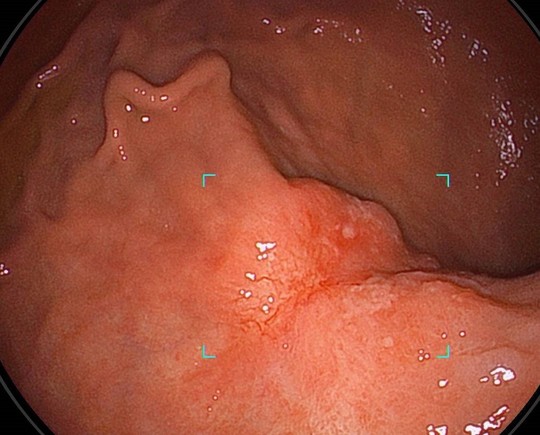

①病変をAIの目で瞬時に捕捉

経験豊富な内視鏡専門医の目に加えて、疲れ知らずのAIが胃病変を瞬時に捕捉し追いかけます。